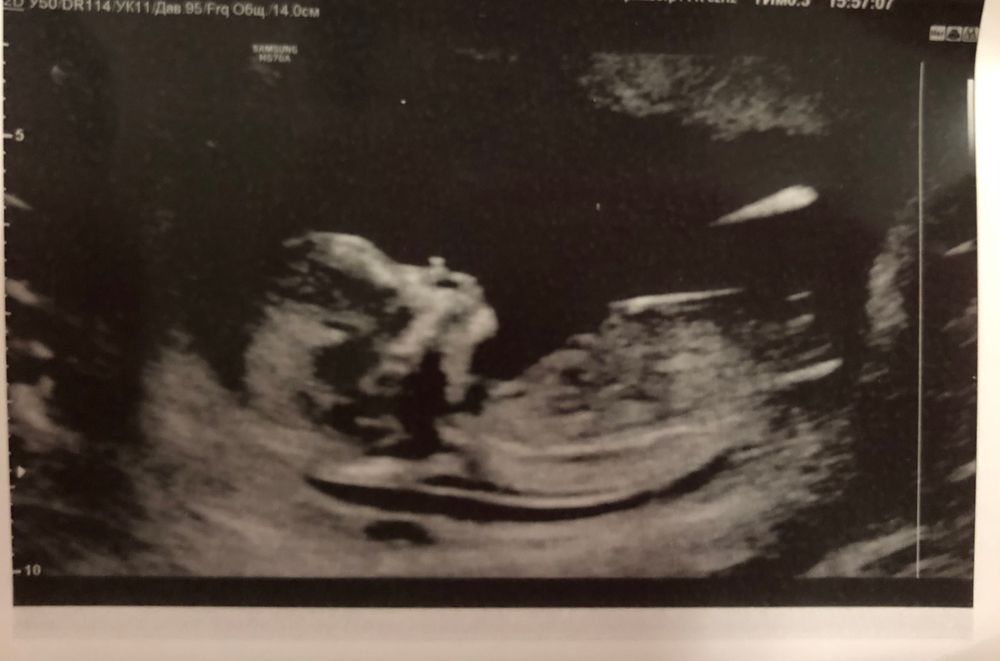

Первый скрининг 13 недель ровно💕

ТВП 2, сердце 154 , отклонений по узи нет. После трансвагинального узи, дома пошла коричневая кровь , завтра напишу своему гинекологу. Надеюсь ничего критичного, возможно сосуд или эрозия.На узи ни гематомы , ни отслойки обнаружено не было.

Пол не сказали , узистка очень усталая и не в настроении , только сухое : «рано», ну ничего страшного , главное укладываемся в норму.Теперь жду кровь 🙏🏼